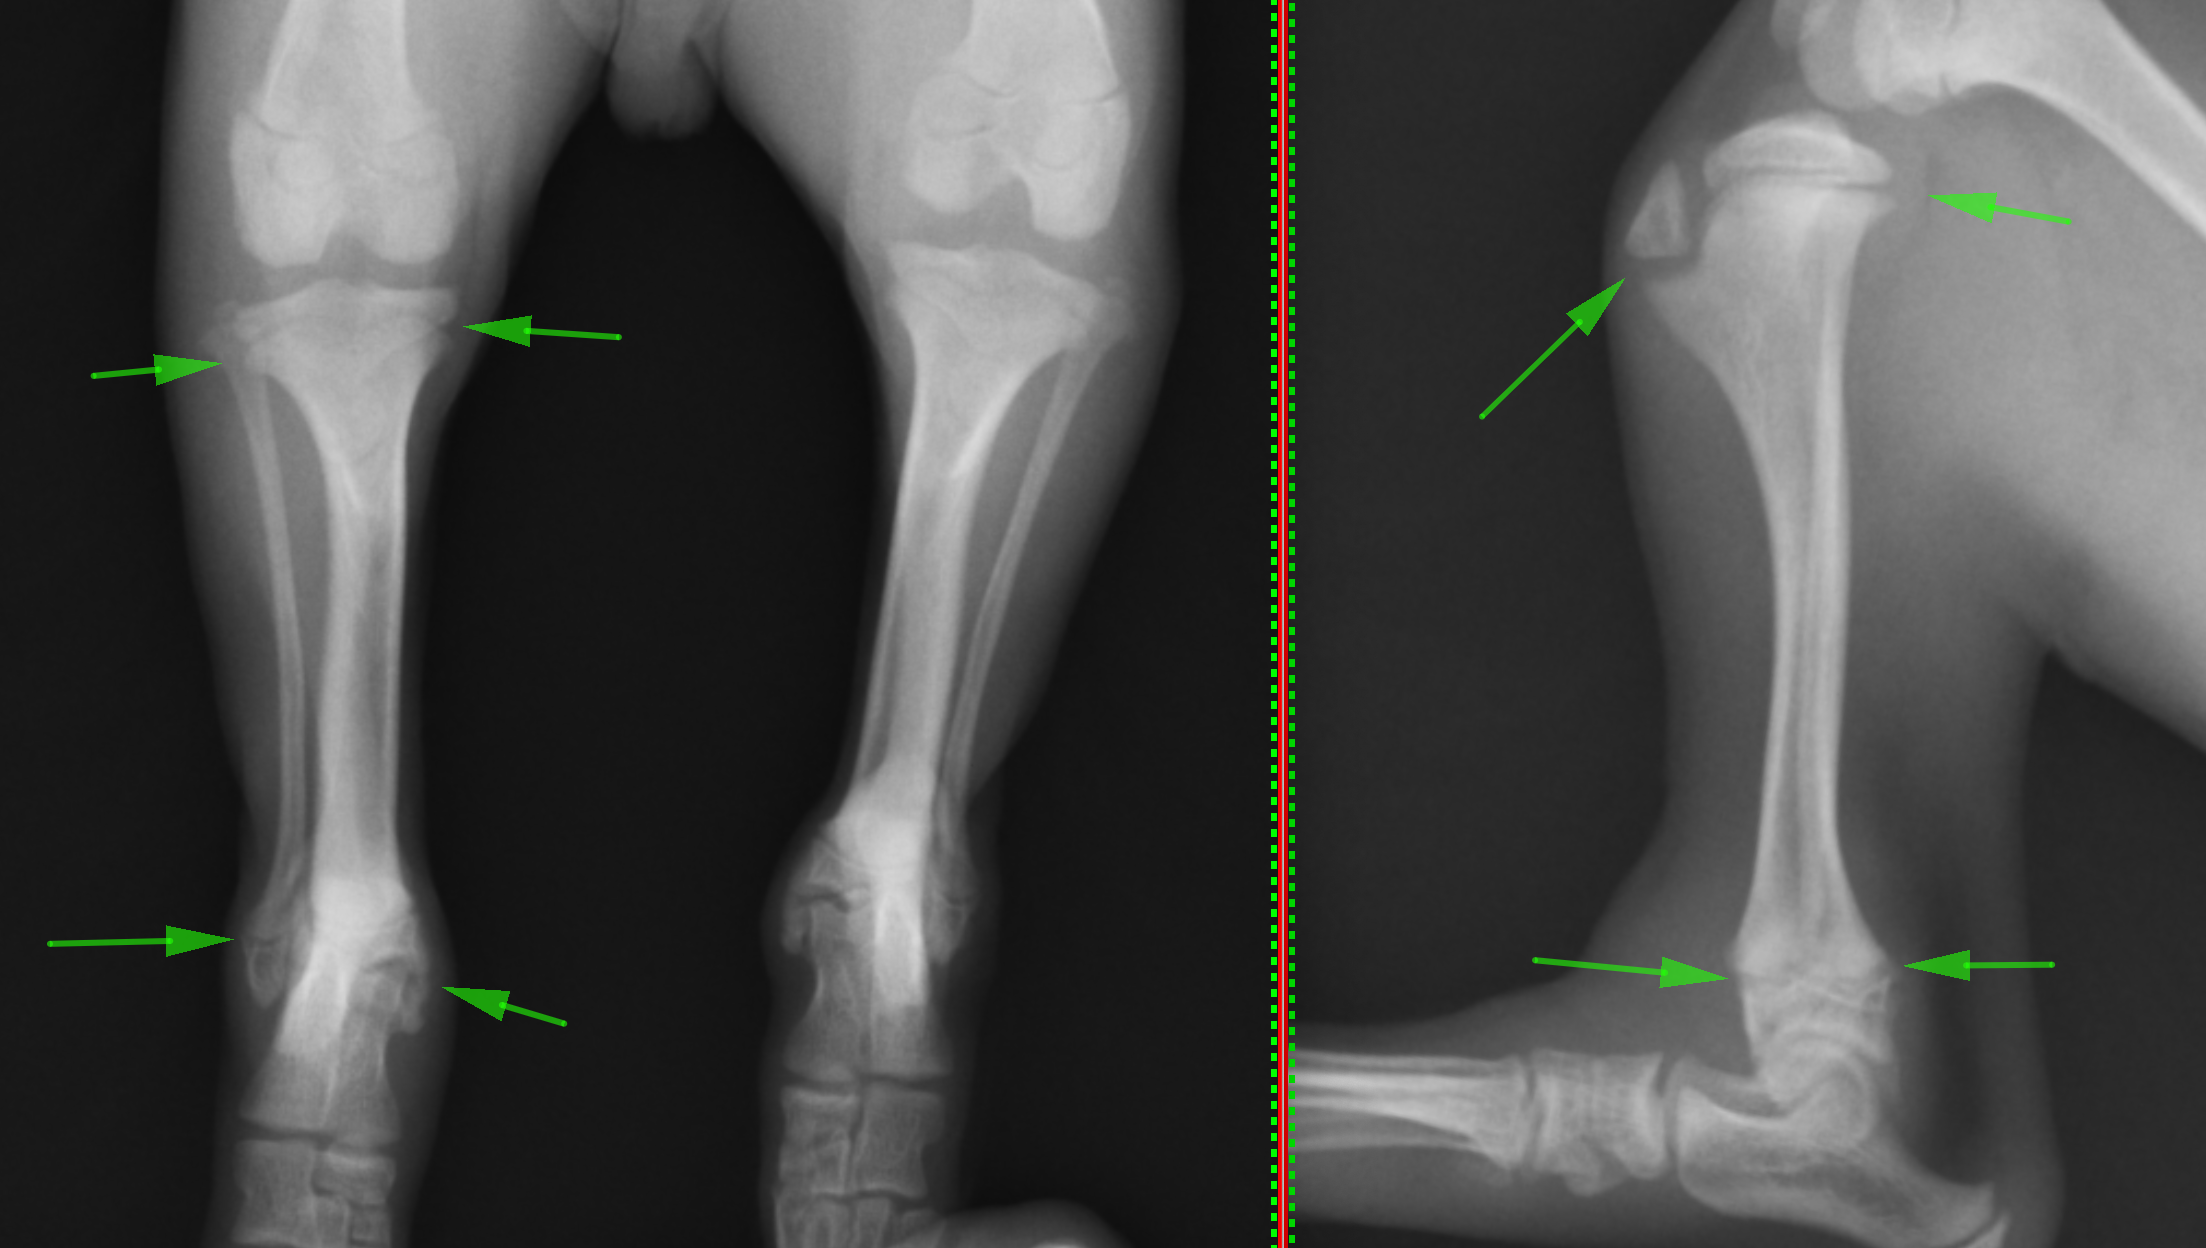

最初のレントゲンでは異常箇所がはっきりと分かりませんでしたが、ストレス撮影(伸ばしたり、曲げたりした状態で撮影すること)を行ったところ骨折箇所がわかりました。

通常の撮影法で撮影したレントゲン画像です。緑矢印の黒く抜けているところが成長板と呼ばれる部分になります。